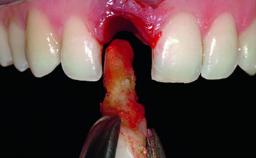

A 36-year-old male patient with a compromised maxillary central incisor was referred by his general dentist for consultation. The patient’s chief complaints were the gradual debonding of a temporary crown on the right central incisor and unsatisfactory esthetics due to an increasing diastema between the right central and lateral incisors. The patient reported a traumatic event some years previously, when a crown had been placed after root-canal treatment. The referring dentist wanted to provide a new crown restoration, but was concerned about the condition of the residual root. Anamnesis was negative for any other dental or periodontal pathology in the remaining dentition. The patient reported taking no medications: He was a smoker (10 to 15 cigs/day) and had realistic esthetic expectations.